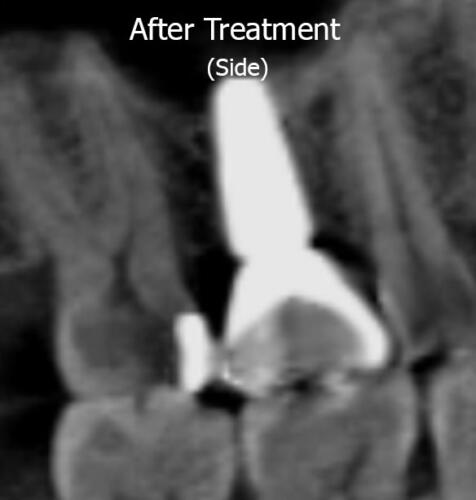

A sinus lift procedure was performed for DM, which lifted the floor of the sinus and resulted in more bone forming (shown by the green dotted line and the transparent overlay of the implant no longer going beyond the green dotted line). This allowed enough bone height in the jaw to facilitate placement of the implant and subsequent crown on top. DM is now able to chew and eat food on high right side, without having a serious sinus infection as a byproduct!